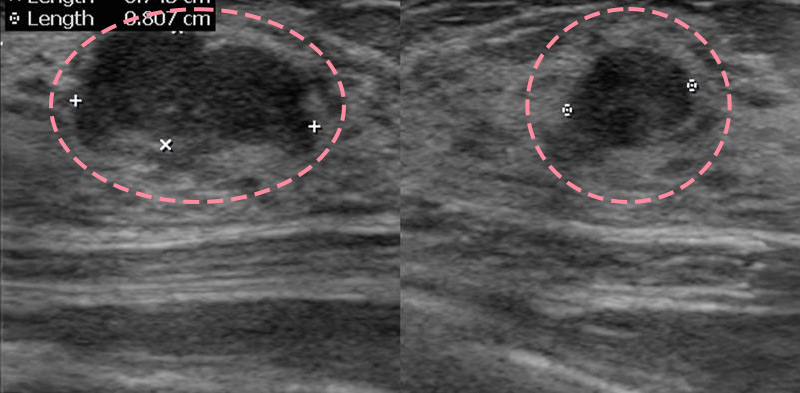

맘모톰시술 후 병리조직검사에서 상피내암(조기유방암)으로 진단되어 대학병원으로 연계해 드린 환자분의 사례입니다. 암을 초기 단계에 찾음으로써 항암치료 없이 간단한 수술을 통해 치료가 가능하였습니다.

한송이영상의학과 한송이 대표원장은 2003년 국내 최초

맘모톰 도입 초기부터 현재까지 직접 진단하고 시술하고 있습니다